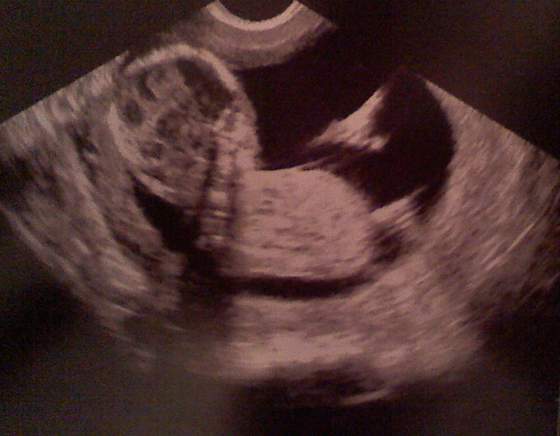

U mnie jest różnica, bo za normalne USG, które mam na wizycie w gina płacę 100złŚliczne dzieciaczki Sivle i Baśka ... wielkie gratki :-)

Zgadzam sie z Wami ,ze takie badanie prenatalne w trybie 3D/4D to niemały wydatek. U mnie kosztuje to 170zł, ale normalna wizyta kosztuje 100zł , więc czy az taka różnica?!